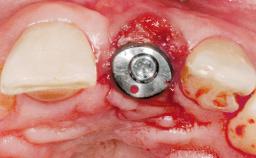

Immediate Flapless Placement of an Implant in a Maxillary Left Central Incisor Site

A 29-year-old female patient presented for treatment to replace the upper left central incisor tooth with an implant- supported restoration. The tooth had been intermittently symptomatic for the previous 12 months. The tooth had originally suffered trauma about 15 years previously. Several endodontic treatments had been performed, including an apicectomy procedure to retain the tooth. The patient was healthy and a non-smoker. She had reasonable expectations in regard to esthetic outcomes and the risk of marginal tissue recession following treatment. At medium smile, the gingival margins of the upper teeth were visible, with a display of 3 to 4 mm of the gingival margins. Gingival recession of tooth 21 and a discrepancy in the gingival levels between teeth 11 and 21 was observable during normal speech and smile.